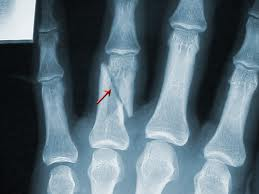

The mainstay of diagnosing finger fractures is an x-ray. Temporary splinting, ice, and pain control are helpful supportive treatments. The type of fracture will determine the treatment. Each fracture pattern has specific characteristics that need to be addressed.

Broken fingers frequently cause immediate pain after trauma and sometimes a deformed finger either at a joint (commonly a dislocation) or through the bone as a fracture. If there is no deformity, a sharp pain usually is felt very specifically at the injury site.

Sometimes you are not sure if the finger is broken, and you try to bend the finger in question. A true fracture usually will be painful, but do not be fooled by a finger that has some range of motion and dull pain. Depending on their stability, some fractures may hurt more than others.